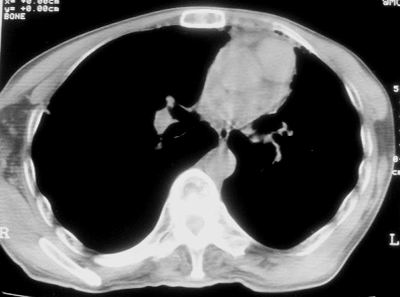

标题: CT11864:男,47岁,反复咳嗽、咯痰、咯血3年,请分析. [打印本页]

患者,男,47岁,反复咳嗽、咯痰、咯血3年,再发5天。痰培养未找到真菌、抗酸杆菌、癌细胞。

左肺上叶体积明显缩小,其内见多发透光区,纵隔向左侧移位,左肺下叶多发班片状病灶,边界模糊,1左肺上叶先天肺发育不全,2左肺下叶肺炎,

左肺上叶结核伴肺纤维化,纵隔移位,左肺下叶感染性病变,建议抗炎抗结核后复查,双肺气肿.

以下是引用xulianj在2008-2-25 21:01:00的发言:[br]左肺上叶结核伴肺纤维化有霉菌球形成,纵隔移位,左肺下叶感染性病变,建议抗炎抗结核后复查,双肺气肿.

考虑:左肺慢纤伴霉菌球形成、双肺全小叶型肺气肿。

1)考虑为:左肺上叶肺结核(空洞形成),伴左下肺感染;不排除霉菌感染可能。2)肺气肿。

左肺上叶结核伴肺纤维化空洞形成并左肺下叶感染,纵隔牵拉移位,建议作进一步检查排除左侧肺霉菌感染可能。